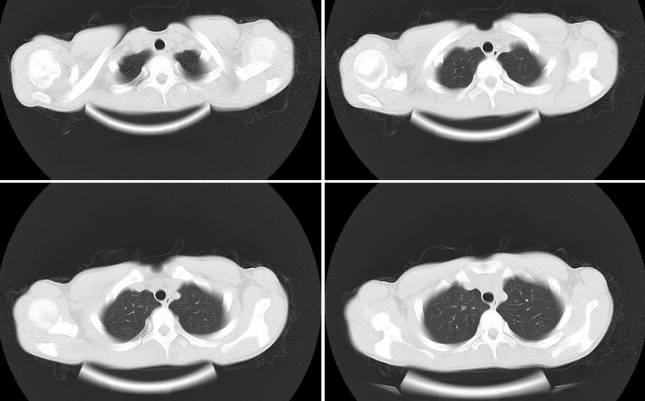

X線檢查、胸部MRI

A:先天性漏斗胸診斷依據一般可以根據胸廓的視診、胸部CT、心電圖等方面的檢查來確認,具體可以到當地的醫院做了解。先天性漏斗胸的形成可能是與遺傳、或者是伴隨有某種先天疾病導致的。患者通常表現為前胸凹陷,肩膀前伸,略帶駝背等症狀。輕微的畸形可以暫時……